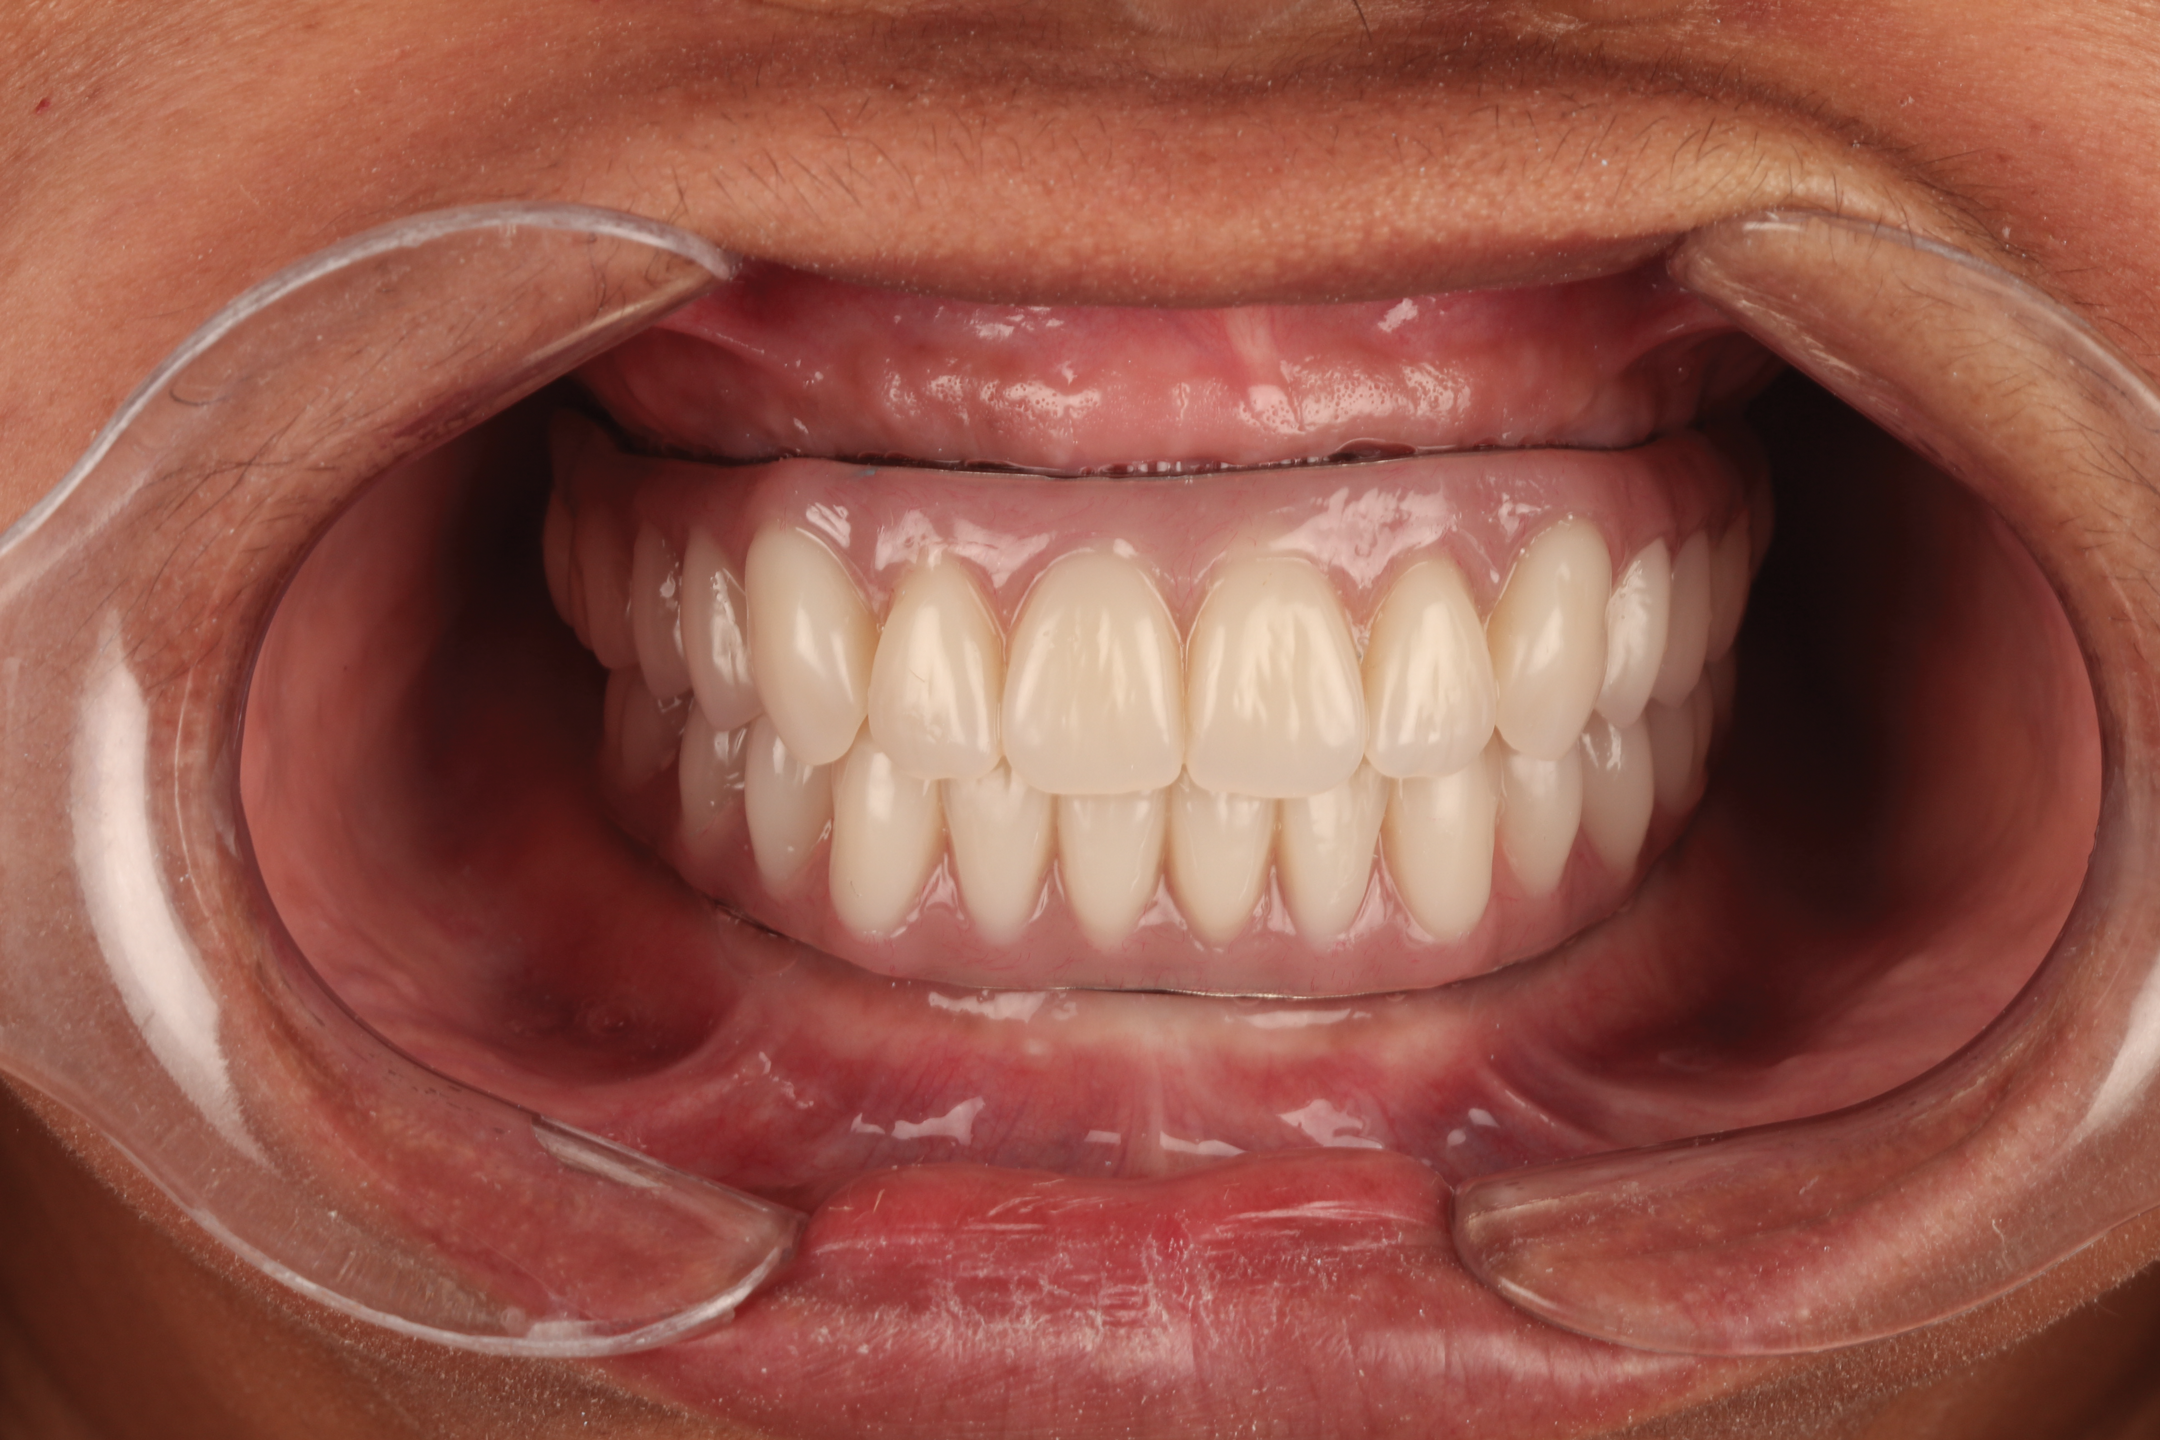

Fig 8. Flangeless denture tried-in showing importance of lip support in this case; facial view (Fig 8) and profile view (Fig 9).

Figure 8

Fig 9. Flangeless denture tried-in showing importance of lip support in this case; facial view (Fig 8) and profile view (Fig 9).

Figure 9

Although patients tend to prefer fixed prostheses over removable ones, facial support is an important factor that may determine the relative advantages of utilizing a removable prosthesis over a fixed one. Facial support can be created or supported by the buccal flange of a denture (Figure 7).25,26 This support can be assessed by inserting the denture and/or duplicate in place with and without a flange. This allows for visualization by the patient and practitioner of the resultant esthetics in a removable or fixed prosthesis. Evaluation of lip support in this manner should be performed with lips at rest and in function and assessed in both frontal and profile views. If lip support is adequate without the flange in place, a fixed prosthesis may be used; however, if lip support without the flange in place is deemed unacceptable, the addition of a flange with a removable prosthesis may be optimal (Figure 8 and Figure 9). Involving the patient in this evaluation and providing visual evidence of the lip support that could be lost as a limitation of a fixed prosthetic option is crucial to providing necessary informed consent for reconstruction of the edentulous maxilla.